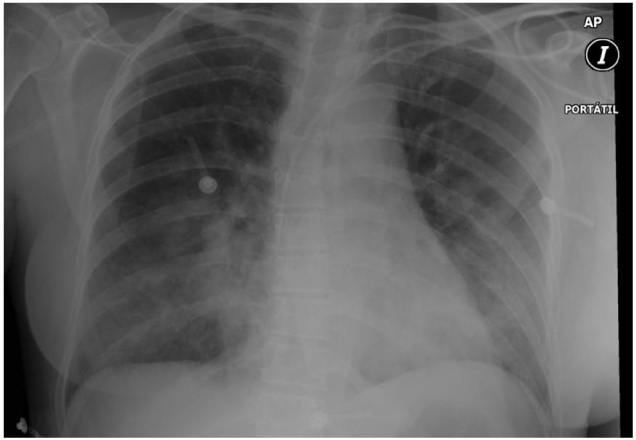

Approximately 500 cc of fluid was recovered through the ETT. Chest X-ray confirmed the diagnosis (Figure 1). Then she was moved to the ICU ward and sedation with Propofol 3 mg/kg/hr and Remifentanil 0, 5 mcg/kg/min were initiated. During treatment with PPV and PEEP, arterial pressured dropped to 80/50 and a dopamine infusion was initiated to keep MAP over 80 mmHg. 4 hours later, a second ABG showed improvement in the oxygenation and pH levels. Plasma electrolytes were: Na 144 mM, K 3, 0 mM, Cl 110 mM Ca++ 5.6 mg/dl. After a negative balance of 7 liters (Figures 2 and 3), respiratory parameters improved and she was extubated in the ICU 7 hours after the event. During the stay in the ICU she also presented dilutional anemia and coagulopathy that did not require transfusions (Hb 7, 4, Hct 26%, INR1.6; PT 44.7%, a PTT, 35 s.) She was discharged from the hospital 7 days later without any serious or irreversible neurological damage of any type.

Figure 1 Chest X-ray diagnosis for confirmation of fluid content.